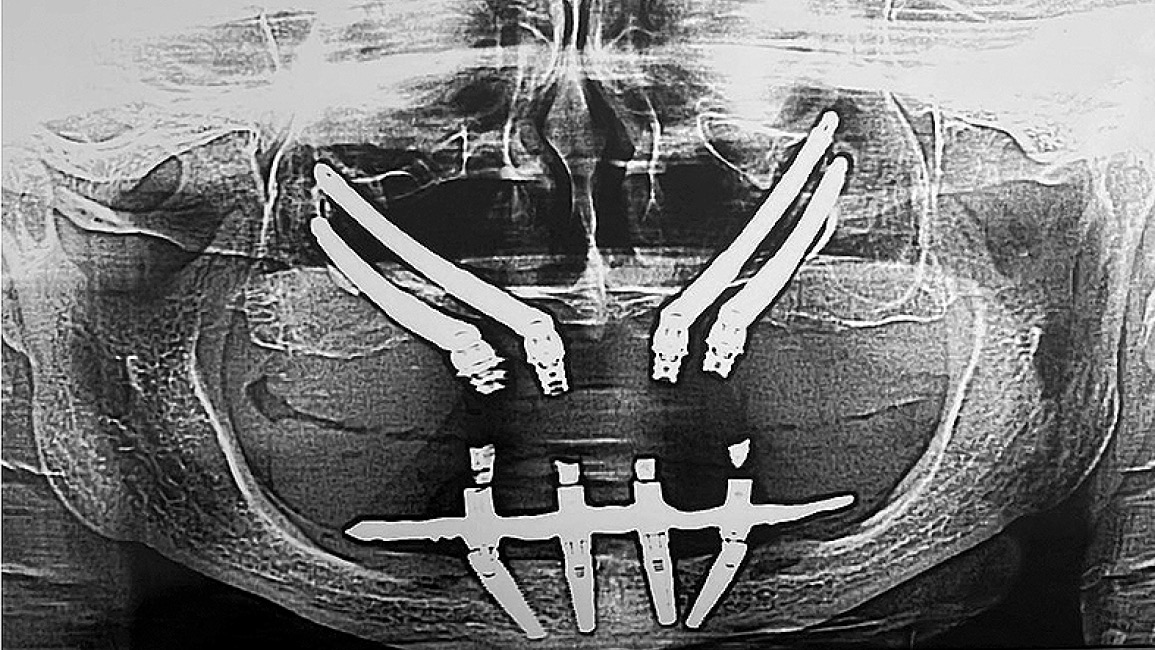

Сразу после хирургического вмешательства провели контрольные рентгенологические исследования посредством ортопантомографии и телерентгенографии головы в прямой проекции, которая более информативна для оценки состояния скуловой кости, верхней челюсти в области имплантатов, верхнечелюстных пазух, их контура дна, а также положения имплантатов (рис. 10).

Рис. 10. Контрольные рентгенологические обследования пациентки сразу после окончания хирургических вмешательств: a — ортопантомограмма; b — телерентгенограмма в прямой проекции.

Fig. 10. Control X-ray examinations of the patient immediately after the completion of surgical interventions: a — orthopantomogram; b — anterior cephalogram.